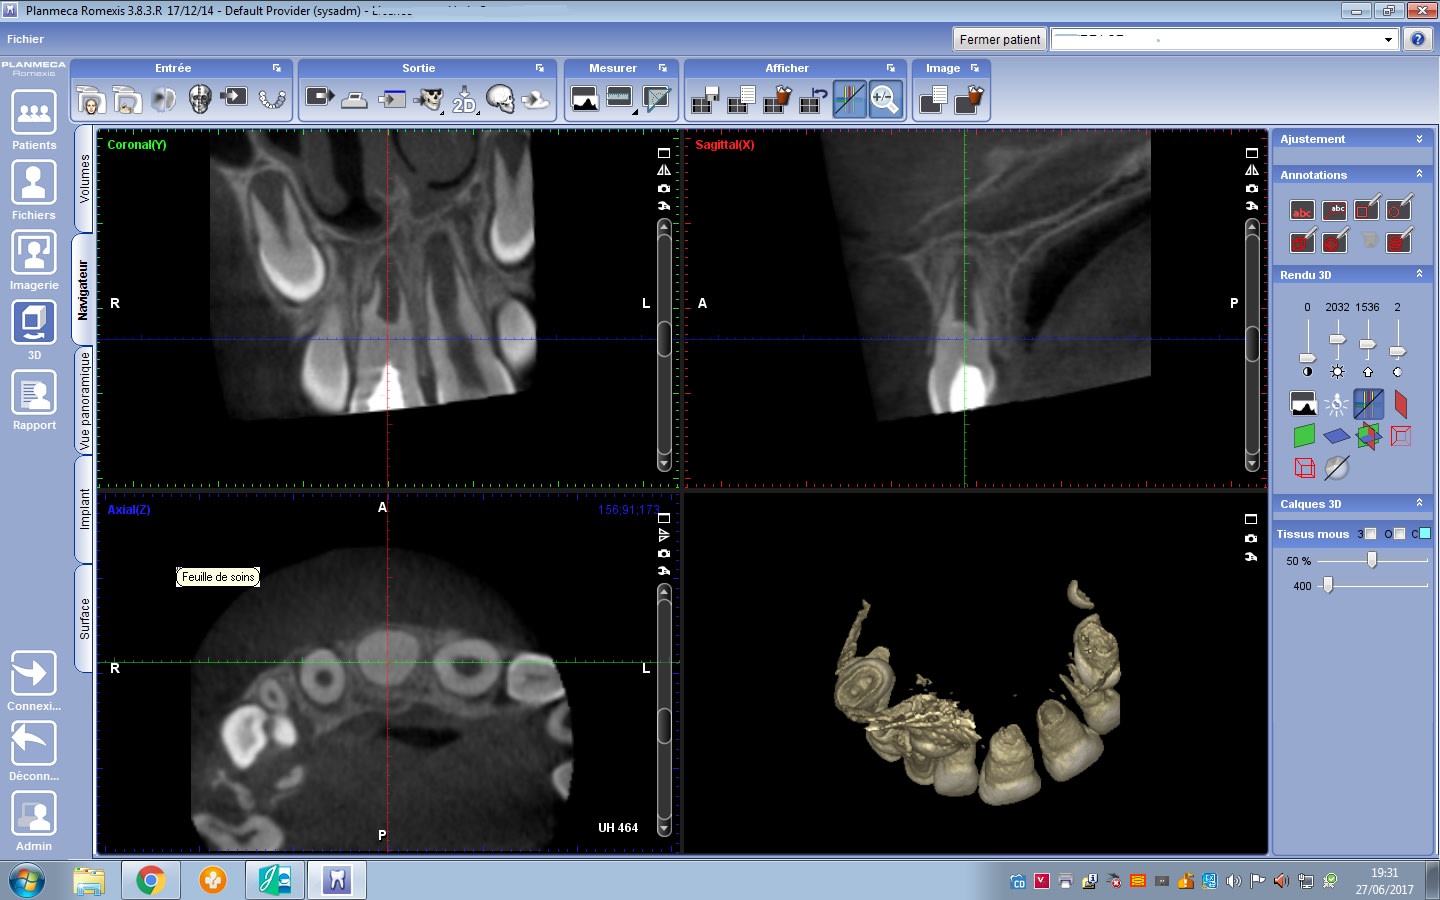

j'ai eu en consultation une fillette de 7 ans qui a subit une chute sur le bloc incisif maxillaire il y a 1 mois.

La dent etant douloureuses, sa dentiste habiluelle s'est lancée dans l'endo mais n'a rien pu faire car trouve "dent calcifiée" et me l'adresse pour ça.

Aujourd'hui: pas de symptomes, test percu negatif et pas de reponse au test de vitalité electrique , mais je ne sais que penser de cette anatomie...

amha, c'est pas la première fois que la gamine fait un trauma sur cette dent...

calcification réactionnelle...perso, je surveille et ne tente de traiter que si apparition de symptômes...

ca ressemble à une cas de "revitalisation" de stéphane simon, parfois ca se produit de manière spontanné suite à un trauma.